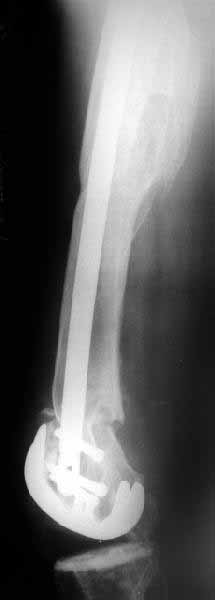

TAC> I can't actually see the osteotomy on either radiograph. Is it more proximal than we see in these radiographs or so well aligned as to be not visible?

The osteotomy was performed through the fracture site. See the attachment.

Well, finally i still performed antegrade nailing. After the distractor was applied, reduction of the recent fracture was obtained "automagically".

But the previous fracture resulted with some posterior displacment of the distal part, so antegrade nail would pass anteriorly, and retrograde nail, even a short one, would have penetrated anterior cortex proximally to the fracture. So perQ osteotomy was necessary to add some mobility at the level, and after that the nail was easily inserted to the distal fragment. The nail is solid, 13 mm, locking screws 6 mm. Locked statically.